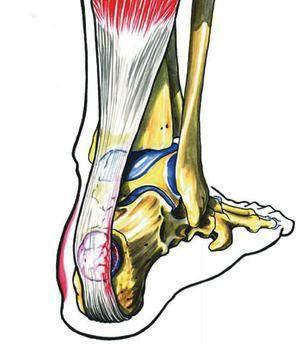

En segundo lugar, tenemos los problemas relacionados con la alta demanda de flexión plantar (técnicamente, las posiciones de «pointe» o «demi-pointe»). En este caso, existe un tendón especialmente vulnerable en la posción de «demi-pointe», que es el Flexor Hallucis Longus, y una situación de conflicto de espacio en la zona retrotalar. Ambos problemas condicionan la aparición del síndrome de impingement posterior que tan frecuentemente vemos en los bailarines.

Imagen del FHL pasando junto al proceso posteromedial del astrágaloImagen del FHL liberado tras el gesto quirúrgico sobre el astrágalo